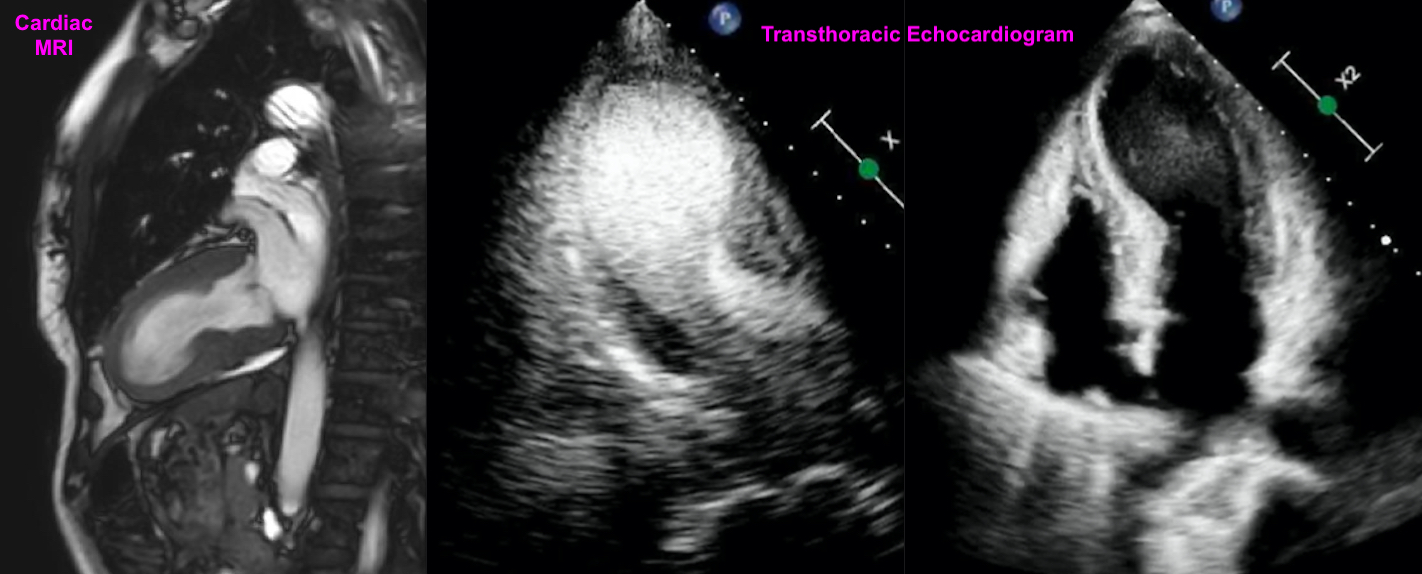

Case Presentation: A 48-year-old female with Hashimoto’s thyroiditis (on Synthroid), prediabetes, and active tobacco use (30 pack-years) who exercises daily presented to the ER with chest pain after a high-intensity workout. The pain radiated to her left arm and neck and intensified to 10/10, associated with palpitations.On exam, she had cool extremities and diaphoresis. Vital signs: BP 93/63, Pulse 87, Temp 36°C, RR 17. An EKG revealed ST elevations in V3-V6 and II, III, aVF. Initial troponin was 696, rising to 1,641 and 2,458. CPK 564, CKMB 9.0. Coronary angiography showed no obstructive coronary artery disease but identified a large myocardial bridge (MB). Transthoracic echocardiogram (TTE) revealed an EF of 15-20%, apical akinesis, apical ballooning consistent with Takotsubo cardiomyopathy (TC), systolic anterior motion of the mitral valve, LV outflow tract gradient of 30-40 mmHg, and an apical LV mural thrombus.Her course was complicated by worsening hemodynamic instability, requiring inotropic support, phenylephrine and esmolol drips. She was weaned off these medications and discharged on metoprolol and anticoagulation for the LV thrombus. She was started on guideline-directed medical therapy (GDMT) for TC.Three days post-discharge, a cardiac MRI showed EF improved to 40%. Repeat TTE two weeks later showed EF of 60% with no wall motion abnormalities. At three months, MRI showed EF of 67% and resolution of the LV thrombus and Takotsubo morphology. The patient quit smoking, adopted a healthy diet, and showed further improvement with optimization of GDMT.